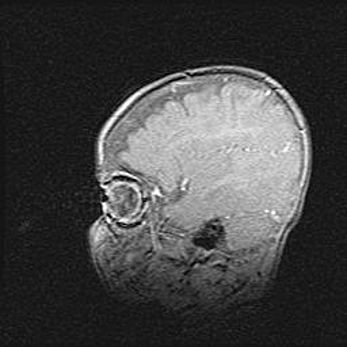

Открытая гидроцефалия.

Возраст: 9 месяцев 12 дней

Вес: 6800 г

Пол: мужской

Окружность головы: 41,5 см

Срок гестации: 28 недель

Гидроцефалия головного мозга у новорожденных имеет характерный признак: опережающий рост окружности головы приводит к визуально хорошо определяемой гидроцефальной форме сильно увеличенного в объёме черепа. Детские неврологи определяют следующие симптомы гидроцефалии у грудничков: выбухающий напряжённый родничок, частое запрокидывание головы, смещение глазных яблок к низу.